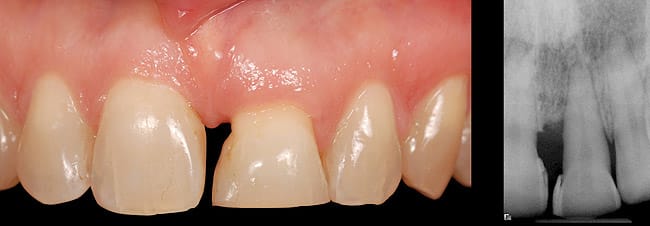

This case involved an ankylosed left central incisor. The patient’s chief complaint was that the incisor was dark and discolored (Figure 9 and Figure 10). Several possibilities were considered, including retaining the tooth or replacing it with an implant. The issue with retaining the incisor concerned the large pulpal canal and the need to aggressively prepare the tooth for a crown in order to mask the dark unesthetic dentin. Another concern was the long-term probability of external root resorption since it was ankylosed. The decision was made to extract and place an implant. The patient had good bone and good soft-tissue positions. The treatment plan was to extract and place the implant with an immediate protocol. The use of an immediate provisional was also considered, but the patient’s deep overbite and his desire to not have to be protective of the implant made the case for doing a bonded provisional. The incision design was done to allow for a facial flap but preserve the papilla. The extraction of the ankylosed incisor required magnification to dissect the tooth from the bone. The implant was placed and the site was grafted with hard and soft tissue. Figure 11 shows the implant, custom healing abutment, CTG, and closure with 7.0 vicryl sutures.

The final soft-tissue form was transferred with the impression by fabricating a custom impression coping, which was made with flowable composite and mimicked the cervical portion of the provisional restoration (Figure 12). The final restoration achieved the patient’s goal of matching the color and esthetic contours with the adjacent teeth. The gingival esthetics were ideal, making the implant undetectable from the natural dentition (Figure 13).